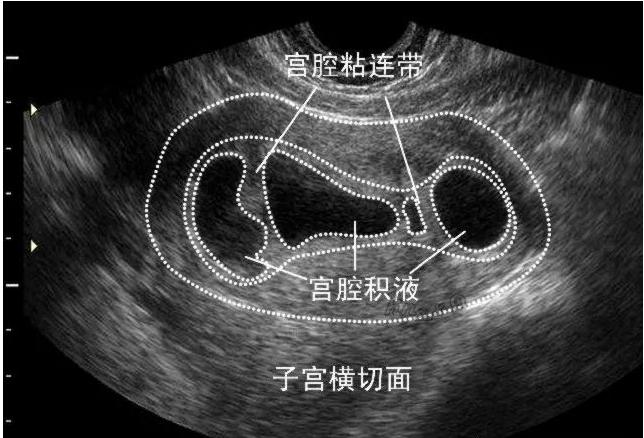

宫腔积水是指输卵管内的液体不能流通,而导致输卵管扩张和积水。有时候,它可能会影响胚胎着床和成长。